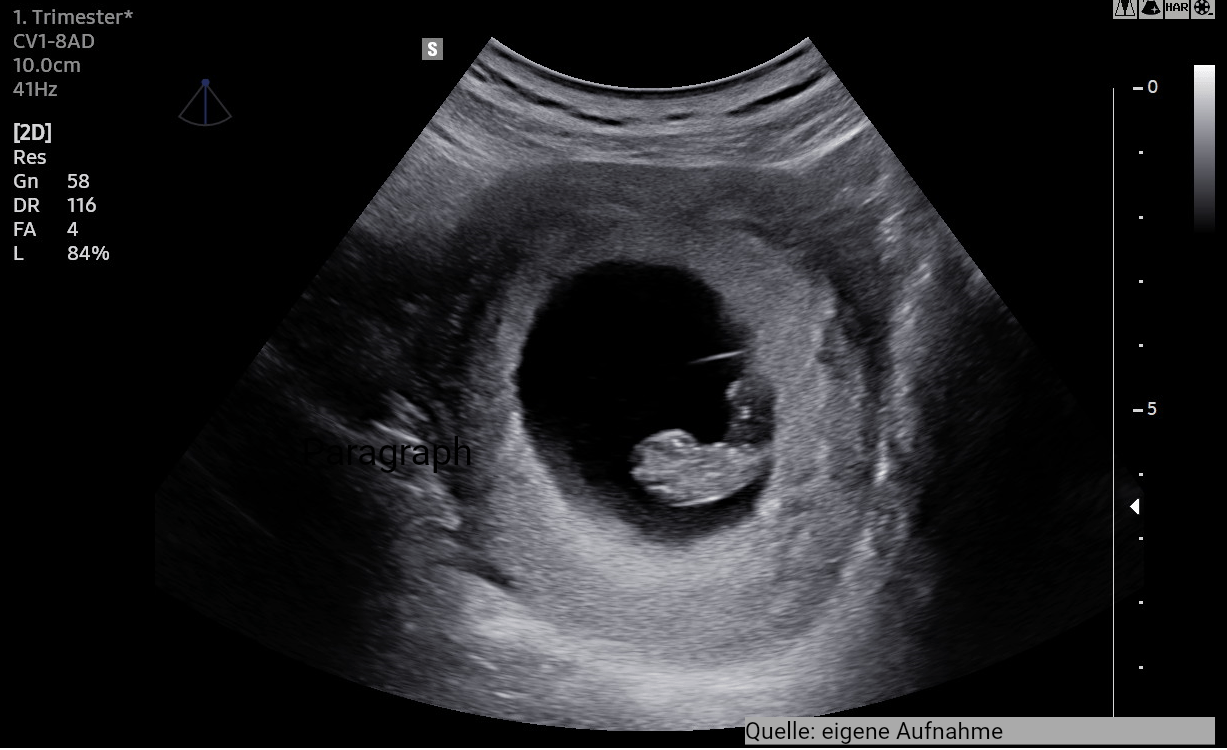

1. Ultraschall (US 1)

Der erste (offizielle) Ultraschall der Schwangerschaft mit entsprechender Dokumentation im MP erfolgt zwischen der 9.-12 SSW.

Der US 1 dient der Bestimmung

- des Schwangerschaftsalters,

- der Vitalität des Embryos,

- der Lagefeststellung in der Gebärmutter

- der Bestimmung der Anzahl der Embryonen

Differenzierte Aussagen zur Morphologie (Gestalt/Struktur) und zu Hinweisen auf eine eventuell vorliegende genetische Störung sind nicht Gegenstand dieser Untersuchung der gesetzlichen Mutterschaftsvorsorge!

Der Ultraschall erfolgt üblicherweise durch die Bauchdecke. Sie können gerne eine Begleitperson ihrer Wahl mitbringen.